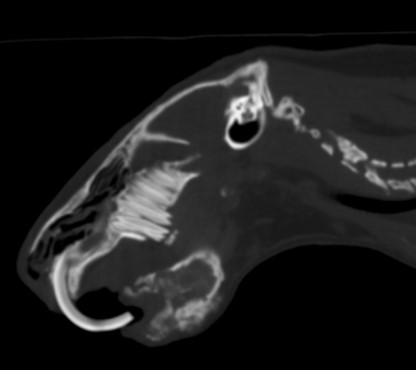

Real Examples of Dental Disease We Treat

A professional dental cleaning removes tartar both above and below the gumline and allows veterinarians to evaluate the health of each tooth.

CT image from a guinea pig patient showing a severe infection affecting the front portion of the lower jaw. The infection damaged the bone supporting the lower incisors, which caused both teeth to fall out. Advanced imaging helps veterinarians evaluate how far the infection has spread within the jaw.